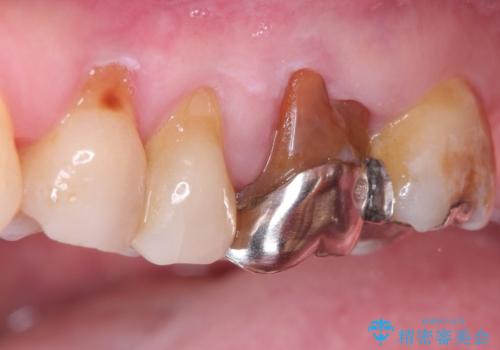

発見の難しい虫歯。根管治療から被せもの治療

- 定期検診にて被せものと歯との隙間に虫歯を発見した患者様です。

根管治療から被せもの治療(ベレッツァ)まで行いました。(根管治療は林院長に依頼)

妥協せずにすべての治療を行うことで最終的な被せものの適合を高める事ができます。